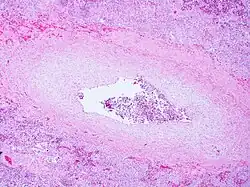

Pulmonary veno-occlusive disease-Intimal fibrosis with marked narrowing of lumen of a large pulmonary vein | |